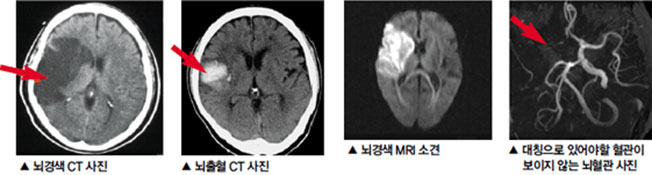

뇌경색 초기증상 10가지

뇌경색의 초기증상은 매우 중요합니다. 신속하게 인지하고 대응하는 것이 생명과 건강을 지키는 데 결정적인 역할을 할 수 있습니다. 오늘은 뇌경색의 초기증상 네 가지에 대해 자세히 살펴보겠습니다.이를 통해 뇌경색을 예방하고, 만약 증상을 경험하게 되면 즉각적으로 대처할 수 있는 방법을 알아보는 시간을 가지겠습니다.👉뇌경색 치료방법 더 확인해보자! 뇌경색이란 무엇인가요?먼저, 뇌경색이 무엇인지 간단히 설명드리고자 합니다. 뇌경색은 뇌의 일부에 혈액 공급이 차단되면서 발생하는 질환입니다. 이로 인해 해당 뇌 영역이 손상되고, 다양한 증상이 나타납니다. 뇌경색은 크게 허혈성 뇌경색과 출혈성 뇌경색으로 나뉘며, 허혈성이 더 일반적입니다. 이 증상은 초기 발병 시점에 따라 치료의 효과가 크게 차이가 납니다.초기증상..